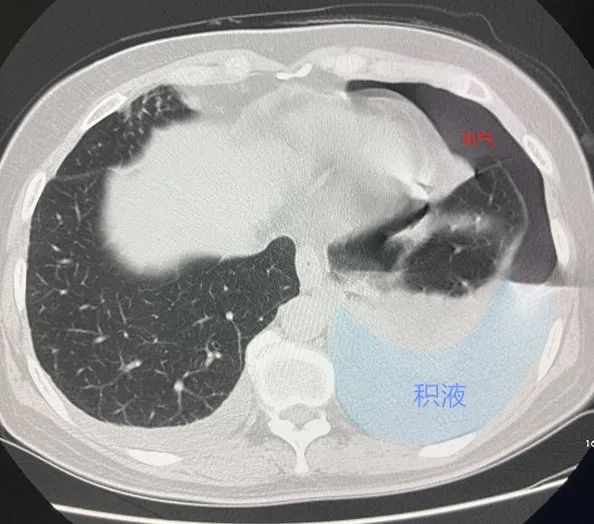

鉴别诊断 消化系统炎症反应,肠道寄生虫,呼吸道感染,心肺系统疾病